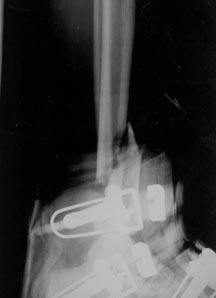

Medical Imaging